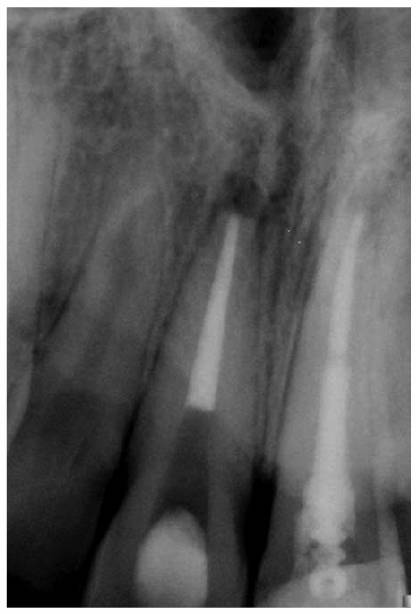

The canals should be filled completely as confirmed by radiographs. The excess

gutta-percha and root canal cement should be removed 2 to 3 mm apical to the

cervical line to prevent discoloration (Figure 19-52). In periodontally involved teeth

where longer crowns are planned, the root-filling materials should be removed

to the bone level. A 2-mm layer of white temporary stopping should be placed

over the gutta-percha.25 Remnants of the cement may be removed with

alcohol. A tooth- colored restorative material (ie, composite resin or glass

ionomer cement) may be used to fill the rest of the canal and chamber when a

post and core are not indicated.

The coronal restoration should be placed as soon as possible after completion

of the root canal treatment if it is not placed at the time when the canals are

filled. There is now building evidence that the coronal restoration is as

important, if not more important, in microbiologically sealing the root canal

system as the root canal obturation material (Figures 19-53A

and B). In a

recent study, Ray and Trope evaluated the radiologic quality of both coronal

and canal obturations.24 It was demonstrated that a tooth with good

coronal and root seals had the best rate of absence of periapical lesions

(91.4%). Good restoration resulted in significantly less incidence of

periapical lesions than good endodontic filling (80% versus 75.7%). Poor

restoration resulted in significantly more periapical lesions than poor

endodontic fillings (48.6% versus 30.2%).

Figure 19-52: Gutta-percha root filling cut back 3 mm apical to the cervical line to prevent discoloration. Two millimeters of white temporary stopping is placed over the gutta-percha. This space will be restored with composite resin. The adjacent tooth will be restored with a crown.